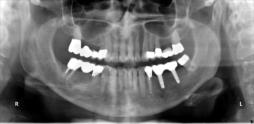

Beispiele für komplexe implantologische Versorgungen aus unserer Gemeinschaftspraxis

(Planung / Endversorgung -- als Röntgenaufnahmen)